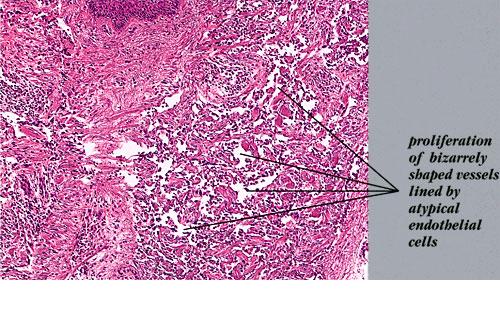

Angiosarcoma = الساركوم الوعائي